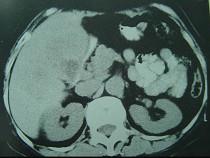

问题 患者,女,51岁,右上腹隐痛1月余,CT扫描如图,最可能的诊断是()

选项 A.胆囊癌(肿块型)侵犯肝脏 B.肝癌侵及胆囊 C.肝转移瘤 D.胆囊周围肝脓肿 E.肝血管瘤

答案 A